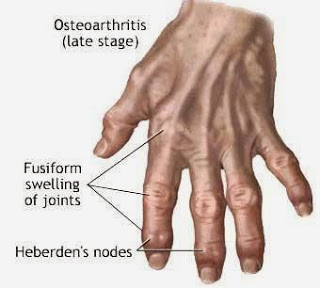

Οστεοαρθρίτιδα

Πολλοί ασθενείς με οστεοαρθρίτιδα ακούν ή αισθάνονται έναν χαρακτηριστικό ήχο (κριγμός) στα γόνατα.

Η οστεοαρθρίτιδα όμως δεν είναι απλά μια πάθηση του χόνδρου. Η βλάβη στο χόνδρο είναι η αρχή μιας αλυσιδωτής αντίδρασης που επηρεάζει όλα τα μέρη της άρθρωσης. Σε χρόνιες καταστάσεις για παράδειγμα σχηματίζονται οστεόφυτα γύρω από την άρθρωση. Ο αρθρικός θύλακος μπορεί να γίνει παχύτερη και να χάσει την ελαστικότητα της. Η μεμβράνη που καλύπτει το εσωτερικό της αρθρικού θυλάκου (αρθρικός υμένας) μπορεί να παρουσιάσει φλεγμονή. Το ίδιο μπορεί να συμβεί και σε τένοντες και συνδέσμους γύρω από την άρθρωση που πάσχει.